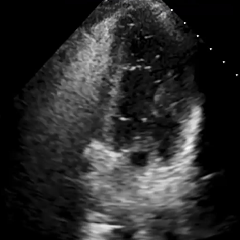

经胸右心声学造影:经左肘静脉注入震荡生理盐水(8mL生理盐水+1mL回抽静脉血+1mL空气经震荡制成),上腔、右房依次显影,造影剂完全充盈右心后,平静呼吸时,左房内即可探及微泡回声,约20-30个/切面/帧;瓦氏呼吸释放即刻,左房内探及微泡回声,不可计数。

术前瓦氏动作后经胸右心声学造影(大量)